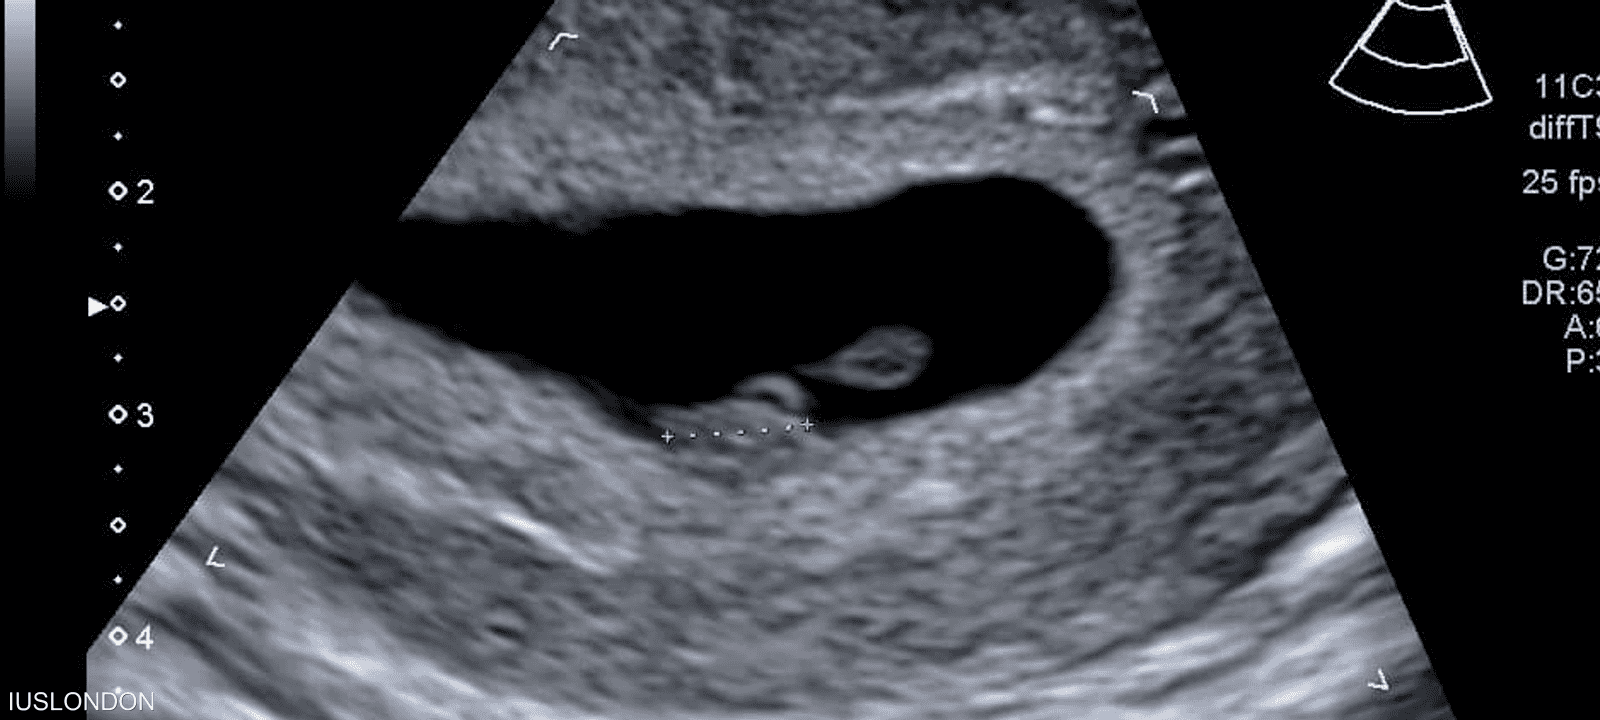

لكن مجموعة من الباحثين الأميركيين تقول إن استخدام الذكاء الاصطناعي لتحليل صور الموجات فوق الصوتية يمكن أن يتنبأ بموعد ميلاد الطفل بدقة تصل إلى 95 في المئة.

وباستخدام برنامج تم تطويره وتدريبه باستخدام أكثر من مليوني صورة بالموجات فوق الصوتية لنساء أنجبن أطفالهن بين عامي 2017 و2020، قام العلماء بقياس مدى قدرة الذكاء الاصطناعي على تقدير ما إذا كان الطفل سيرى النور في موعد ولادته أم لا.